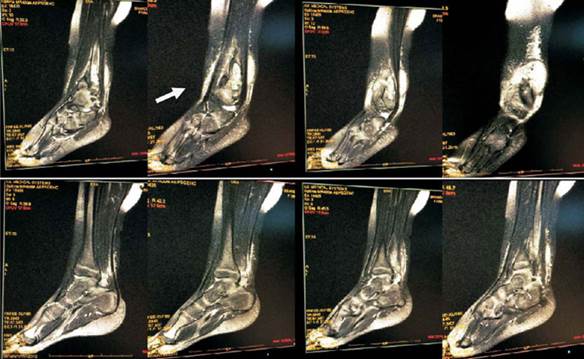

A las 72 horas del ingreso se realiza resonancia nuclear magnética (RNM) de tobillo derecho: en T1 en tercio inferior del peroné e interlínea articular tibiotarsiana imágenes hipointensas, lesión en astrágalo con imagen en sacabocado. En T2 imágenes hiperintensas (Figura 2, Figura 3 y Figura 4).